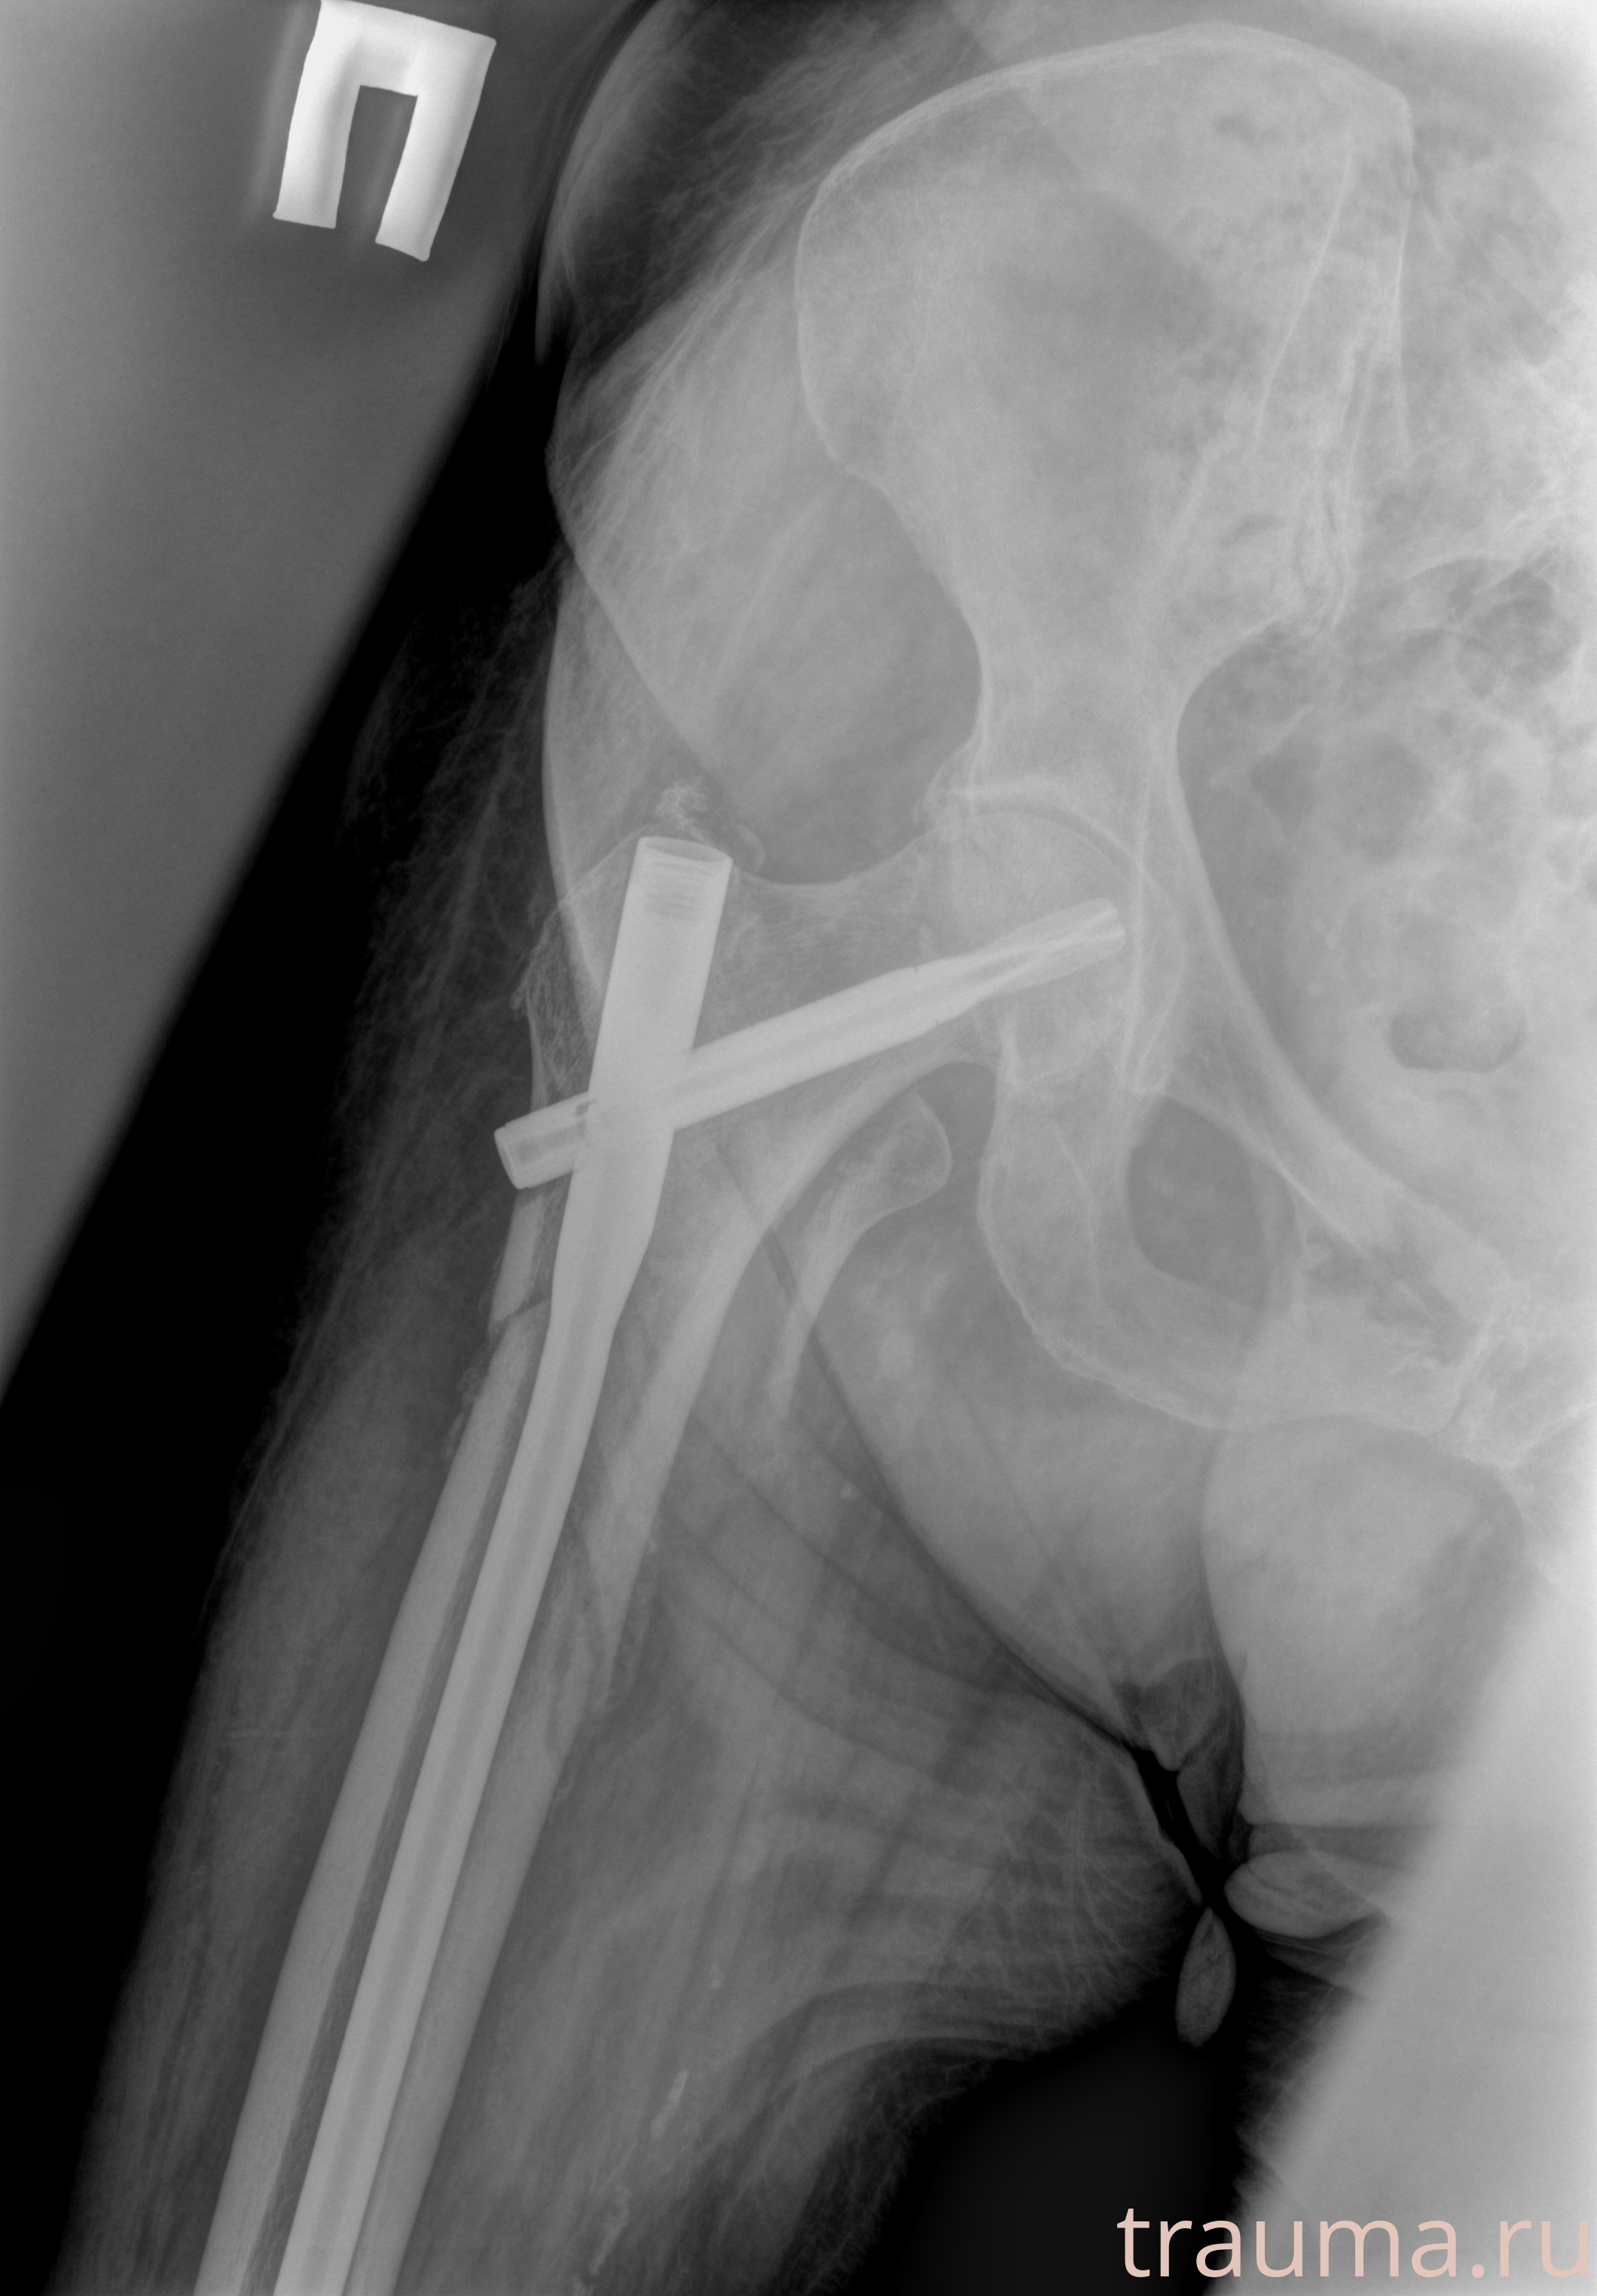

Рентгенограммы

Рентген на дому: по вашему адресу приезжает врач-рентгенолог, травматолог-ортопед с мобильным рентгеновским аппаратом, проводит диагностику травмы или заболевания, делает необходимые рентгенограммы, дает рекомендации по дальнейшему лечению. Получить качественные снимки в домашних условиях возможно благодаря уникальной методике, разработанной МосРентген Центром для института  Склифосовского